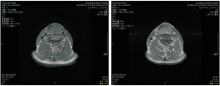

颈部增强CT(2010-12-28):左侧声带小结节, 符合声门癌, 考虑累及前联合、右侧室带, 见图1。

入院诊断:左侧声门型鳞状细胞癌cT1bN0M0Ⅰ 期。